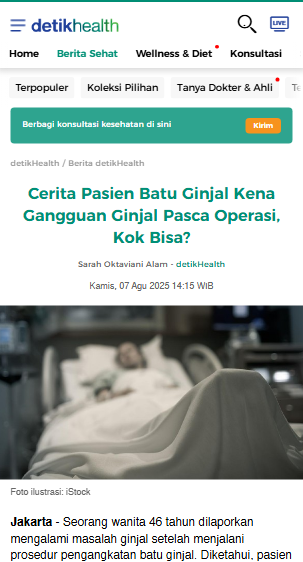

JANGAN BIARKAN GANGGUAN GINJAL SEMAKIN PARAH & BERAKHIR DENGAN OPERASI !!!

Jangan Tunggu Sampai Penyakit Ginjal Semakin Menyebar !

Ini Kata Mereka Yang Sudah Berhasil Sembuh dari Gangguan Ginjal